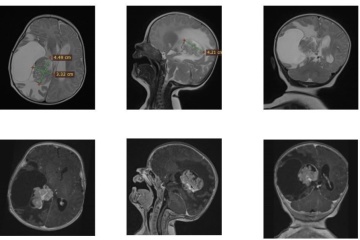

Нейрохірурги львівського Клінічного центру дитячої медицини врятували двомісячну дитину, видаливши їй пухлину в мозку.